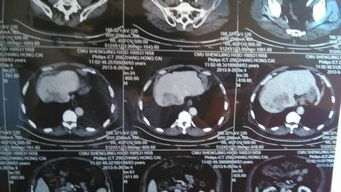

病情分析:您好,您的情況主要是谷丙轉(zhuǎn)氨酶指標(biāo)過高,這樣的話一般是重點(diǎn)進(jìn)行上腹部的CT掃描,目的是了解肝臟有無異常病變。